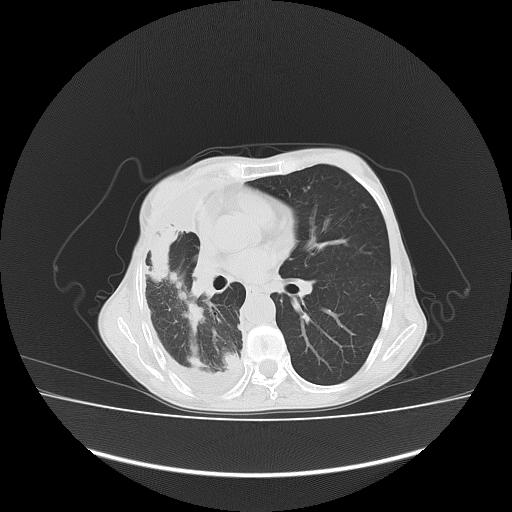

可见多发肺内病灶,且胸膜病灶较多有圆球状而非丘状,多考虑胸膜转移瘤伴胸腔积液,右侧胸廓缩小固定,且部分病灶呈丘状,尚不除外恶性胸膜间皮瘤伴肺内转移

右侧胸膜增厚,局部呈结节状增厚,右侧胸腔少量积液。双肺未见确切肿块影。纵隔未见淋巴结肿大。气管、支气管通畅。考虑右侧胸膜间皮瘤(恶性?)可能性大。不除外癌性胸膜炎。

恶性胸膜间皮瘤伴肺内转移可能性大;或胸膜、肺内均为转移瘤,左肺下叶亦见多发小结节影。

右侧胸廓塌陷,右侧胸膜广泛增厚并见多发胸膜结节,右侧少量胸腔积液并包裹。

右侧广泛胸膜增厚,局部呈结节状增厚,右侧胸腔少量积液。双肺未见确切肿块影。纵隔未见淋巴结肿大。气管、支气管通畅。考虑右侧胸膜间皮瘤(恶性?)可能性大。支持!

右胸腔结节均考虑来自胸膜(部分来源于叶裂),考虑胸膜间皮瘤或转移瘤.